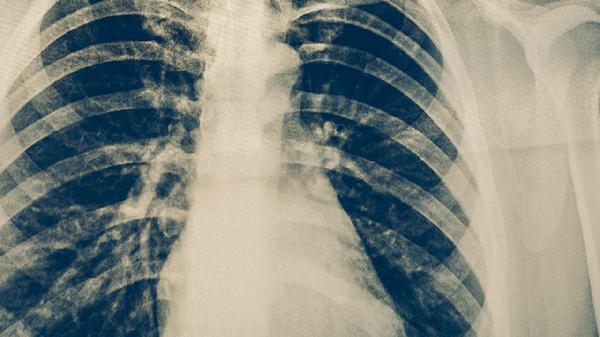

肺结核患者需坚持6-8个月的规范用药,不可自行停药或减量。治疗期间应保持高蛋白饮食,适量补充维生素和矿物质,避免吸烟饮酒。定期进行痰涂片检查和胸部影像学复查,密切观察药物不良反应。如出现皮肤黄染、视力模糊或持续发热等症状需立即就医。居住环境需保持通风良好,密切接触者应进行结核菌素试验筛查。